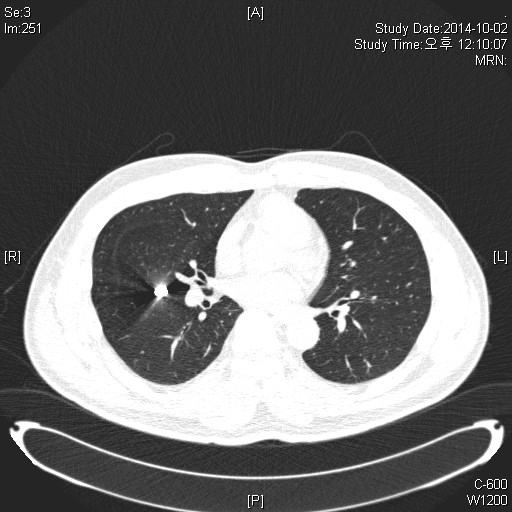

M/54, Abnormal CXR on Operability consult

¾È°ú¿¡¼­ ¼ö¼ú °èȹ Áß Chest PA »ó¿¡¼­ ¹ß°ßµÈ calcification À¸·Î ½ÃÇàÇÑ Chest CT ÀÔ´Ï´Ù.

È£Èí±â Áõ»óÀº ¾ø¾úÀ¸¸ç, ÀÌÀü ±º´ë¿¡¼­ ÆøÅºÀ» ¸ÂÀº °ú°Å·ÂÀÌ ÀÖ½À´Ï´Ù.